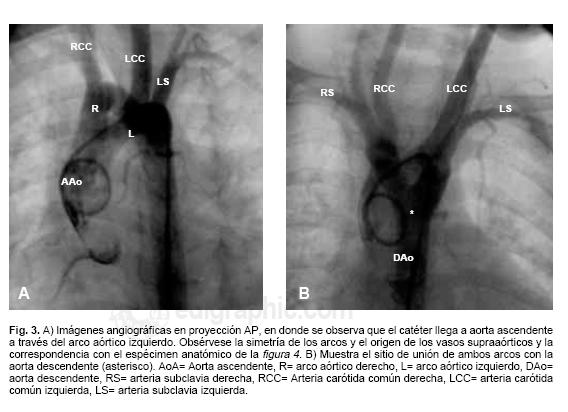

Anillo vascular MedlinePlus enciclopedia m dica illustraci n best sale, Anillos vasculares best sale, Anillos vasculares best sale, Anillo vascular. Web de las cardiopat as Cong nitas best sale, Anillos vasculares best sale, Anillos vasculares best sale, Caracter sticas y manifestaciones cl nicas de los anillos best sale, Anillos vasculares best sale, ANILLOS VASCULARES EN PEDIATR A. PRESENTACI N DE 2 CASOS best sale, Anillos vasculares best sale, Figure 1 from Anillo vascular por doble arco a rtico sim trico best sale, Anillos vasculares Radiolog a PPT best sale, Caso cl nico. Anillos Vasculares best sale, Anillo vascular por doble arco a rtico sim trico. Reporte de un caso best sale, PDF Anillo vascular completo diagn stico prenatal de doble arco best sale, VASCULAR RINGS MAGNETIC RESONANCE FINDINGS best sale, Anillos Vasculares y Slings PDF PDF Aorta Tos best sale, PDF S ndrome de Rubinstein Taybi asociado a anillo vascular best sale, Anillo vascular 15 anos de experiencia en el Hospital Infantil de best sale, Diagn stico y tratamiento de persistencia de cuarto arco a rtico best sale, Anillo vascular por doble arco a rtico sim trico. Reporte de un caso best sale, Reparaci n de sling de la arteria pulmonar sin necesidad de bypass best sale, PDF Anillos vasculares obstrucci n de v a a rea en ni os. Serie best sale, Figure 2 from Anillo vascular por doble arco a rtico sim trico best sale, Anillo vascular 15 anos de experiencia en el Hospital Infantil de best sale, Anillos vasculares completos Anales de Pediatr a best sale, ANILLOS VASCULARES HALLAZGOS POR RESONANCIA MAGN TICA best sale, Los Anillos vasculares Una amenaza creciente para la v a best sale, Anillo vascular por doble arco a rtico sim trico. Reporte de un caso best sale, Vascular rings and pulmonary arterial sling from respiratory best sale, Anillos vasculares nuestra experiencia en 18 casos best sale, Anillo vascular. Diagn stico por ecocardiograf a en periodo fetal best sale, Anillo vascular por doble arco a rtico sim trico. Reporte de un caso best sale, Figure 2 from Anillo vascular por doble arco a rtico sim trico best sale, Anillos vasculares y compresi n traqueo esof gica 15 a os de best sale, Figure 1 from Anillo vascular por doble arco a rtico sim trico best sale, Doble arco a rtico. Reporte y an lisis de caso en un paciente best sale, S ndrome de Rubinstein Taybi asociado a anillo vascular completo best sale, Multidetector Computed Tomography for Congenital Anomalies of the best sale, PDF Anillos vasculares como diagn stico diferencial del asma best sale, Anillos vasculares nuestra experiencia en 18 casos best sale, Anillos Vasculares y Slings PDF PDF Aorta Tos best sale, Vascular Rings Practice Essentials Anatomy Pathophysiology best sale, Multidetector Computed Tomography for Congenital Anomalies of the best sale, Resumen topografia miembro inferior Anatom a e Im genes best sale, Vascular Rings Practice Essentials Anatomy Pathophysiology best sale, Cardiopat as cong nitas. Anillo vascular best sale, Anillos vasculares completos Anales de Pediatr a best sale, Anillos vasculares y compresi n traqueo esof gica 15 a os de best sale, Multidetector Computed Tomography for Congenital Anomalies of the best sale.